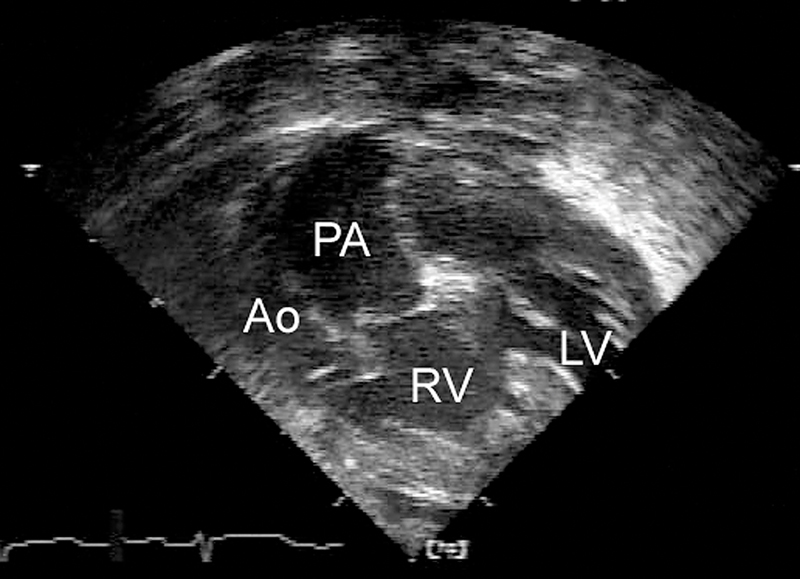

فحوصات تشخيصية لبعض امراض القلب والشرايين التاجية